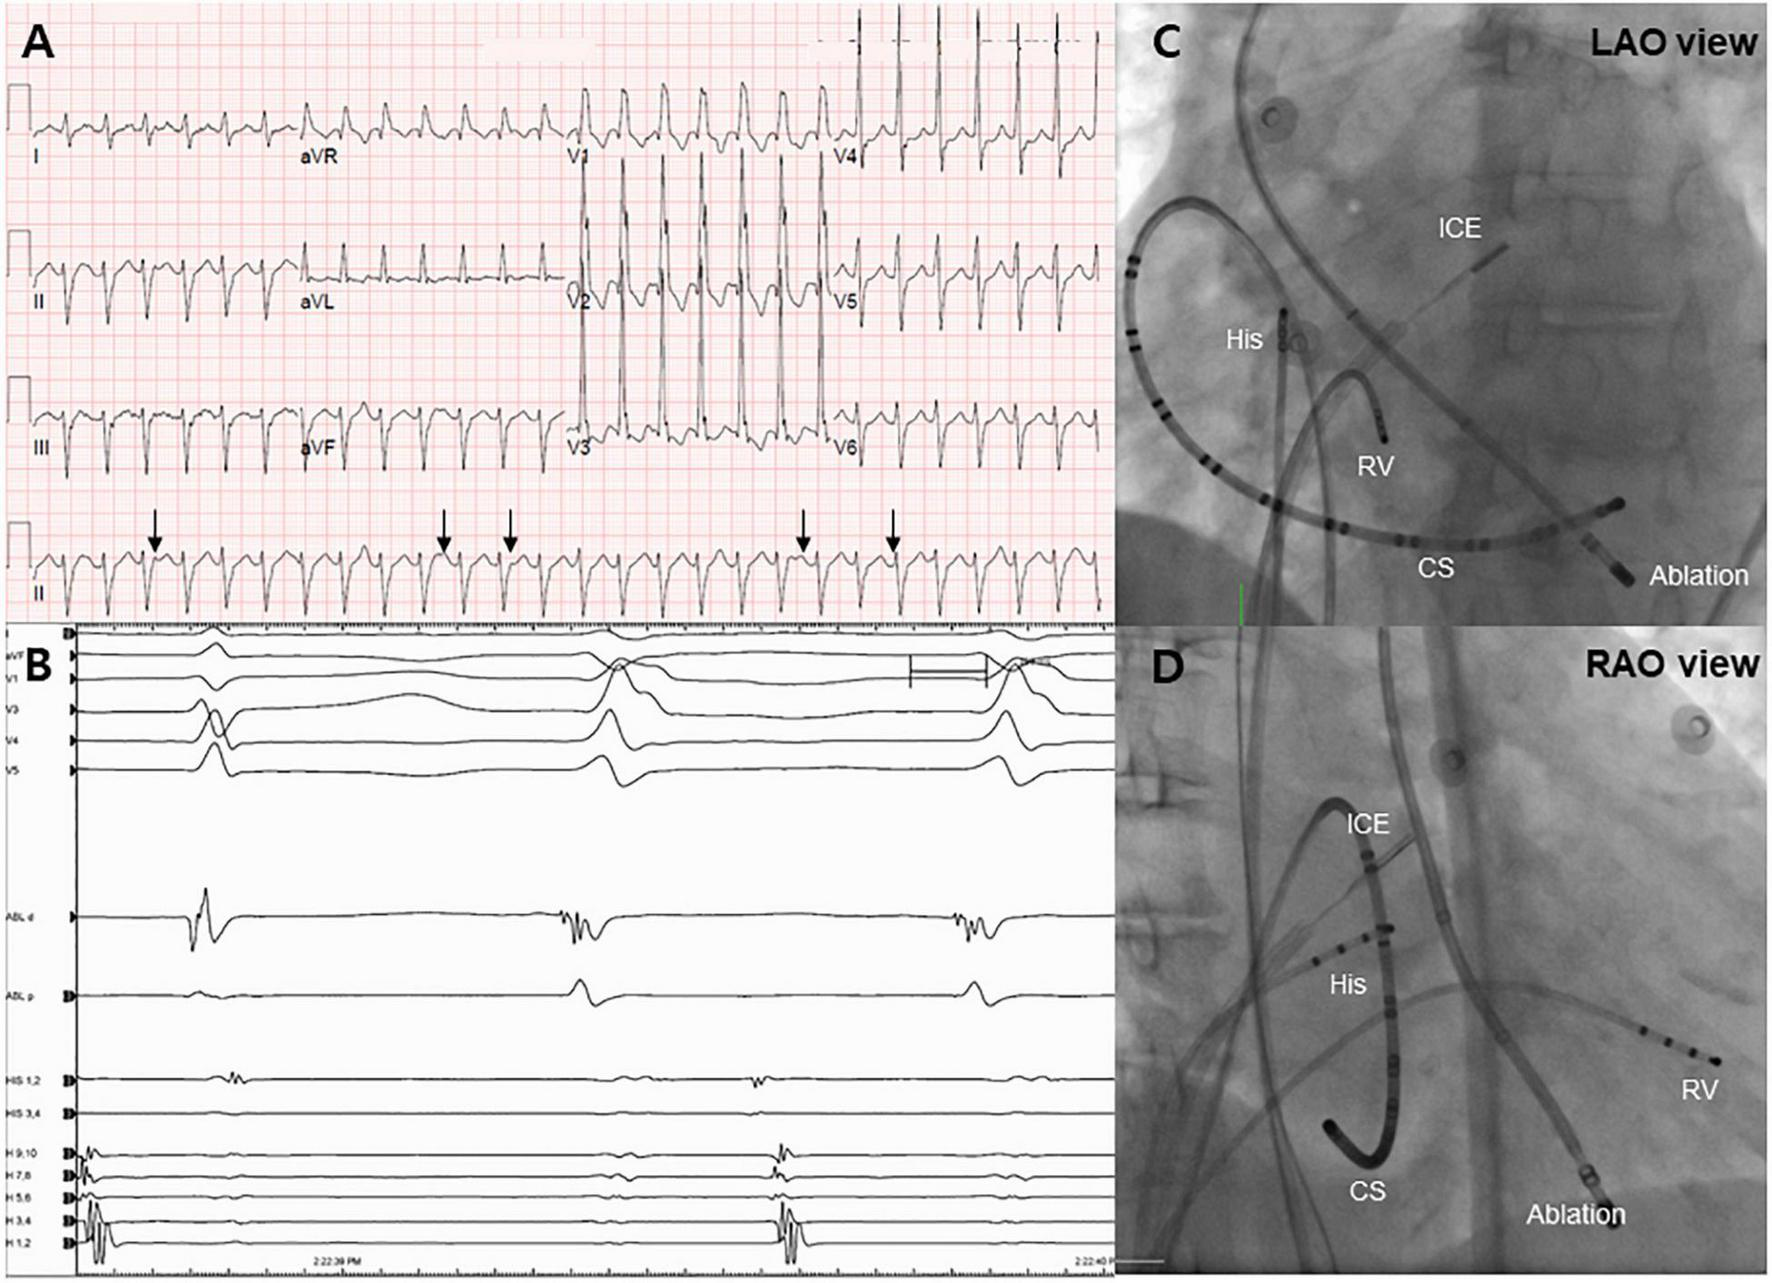

FIGURE 1

Electrocardiogram and endocardial mapping. (A) Electrocardiogram of monomorphic ventricular tachycardia showing ventriculoatrial dissociation (black arrows). (B) Intracardiac electrogram revealing an early signal (−40 ms) before the QRS complex during the ventricular tachycardia rhythm. (C,D) Right and left anterior oblique projections of endocardial mapping using intracardiac echocardiography. CS, coronary sinus; RV, right ventricle.

Following admission to the cardiac intensive care unit, the patient underwent a percutaneous left-sided stellate ganglion block with bupivacaine, a cardiac sympathetic intervention suppressing sympathetic activity for controlling VT. However, the cardiac sympathetic intervention was unsuccessful. Given that the VT remained unresolved and the driving cause of electrical instability was unclear, radiofrequency catheter ablation was decided as the most appropriate treatment strategy. Endocardial electroanatomical mapping of the LV using a CARTO-3 system (Biosense Webster) was performed through both transseptal and retroaortic approaches using a multi-electrode catheter. The procedure was performed using intracardiac echocardiography (ICE) through a transseptal approach and viewing the LV structure in real-time. The ablation catheter was positioned through the retroaortic approach. During endocardial mapping, intracardiac electrograms showed fractionated potentials around the posteromedial papillary muscle with the earliest activation (−40 ms) (Figures 1B–D). Endocardial bipolar voltage mapping revealed no scarring (0.5–1.5 mV), and the activation map was consistent with an exit site in the posteromedial papillary muscle region. Under direct ICE visualization (Figure 2A), endocardial ablation using an irrigated-tip catheter (SmartTouch, Biosense Webster) and 40 W was applied to target the earliest site that showed the initial Q wave in the unipolar signal with 10–15 g of contact force (Figures 2B,C). During the first ablation, the VT was terminated for 30 s with an inaudible steam pop recorded by ICE (Figure 2D and Supplementary Video 1), and a sudden rise in electrical impedance was not noted. After confirming that no evidence of perforation or tissue defects were present in the first ablation site, multiple circumferential ablations were performed in the area surrounding the posteromedial papillary muscle without further steam pops. Repeated programmed electrical stimulation failed to induce VT following the ablation. Before the end of the procedure, the ICE operator confirmed that there was no evidence of procedure-related complications. The transthoracic echocardiography performed the next day showed no evidence of mitral regurgitation or tissue defects in the ablation sites (Figure 3A).